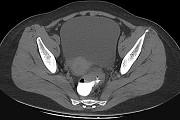

问题 男,67岁,排便习惯改变,血便三个月入院,CT检查如图所示,下列说法错误的是 ( )

选项 A.直肠肠腔局限性增厚 B.其表面欠光整,边界欠清晰 C.可做直肠指检及活检以确定病变性质 D.此为直肠息肉 E.此为直肠癌

答案 D